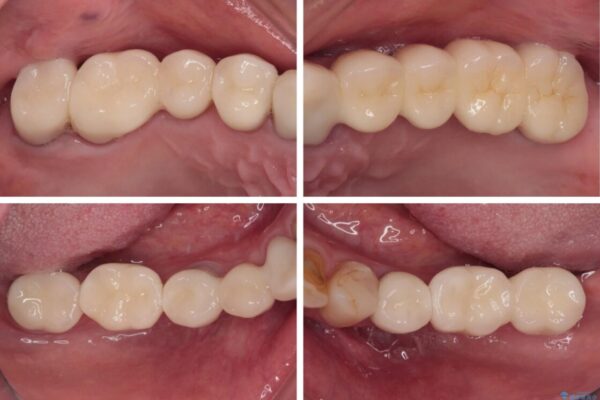

治療後

• 放置したインプラントとインビザライン 全顎リカバリー治療 治療後画像